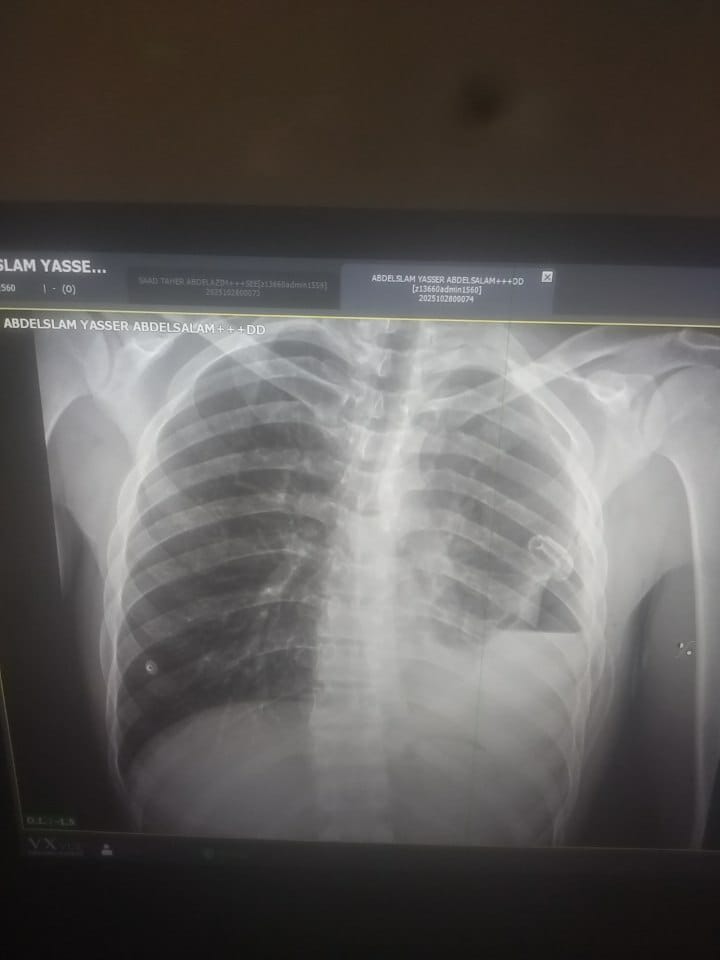

نجح الفريق الطبي بوحدة المناظير بمستشفى صدر المنصورة في إجراء منظار تجويف صدري لشاب يبلغ من العمر 25 عامًا، كان يعاني من آلام متكررة بالصدر وارتفاع في درجة الحرارة وصعوبة في التنفس.

وأوضح الدكتور محمد السعيد، مدير مستشفى صدر المنصورة، أن المريض كان يتردد على العيادات الخارجية والمستشفيات لفترة طويلة بسبب الأعراض المستمرة، وبعد إجراء الفحوصات اللازمة من إشاعات وتحاليل، تبين وجود انسكاب بلوري على الرئة، وتم على الفور عرض الحالة على فريق وحدة المناظير برئاسة الدكتور السيد فهمي، استشاري الصدر، حيث تم إجراء المنظار بنجاح، وتركيب الأنبوبة الصدرية، وأخذ العينات اللازمة لإجراء التحاليل الباثولوجية والميكروبيولوجية لتحديد سبب الحالة بدقة، وتماثل المريض للشفاء بعد تلقي العلاج المناسب.